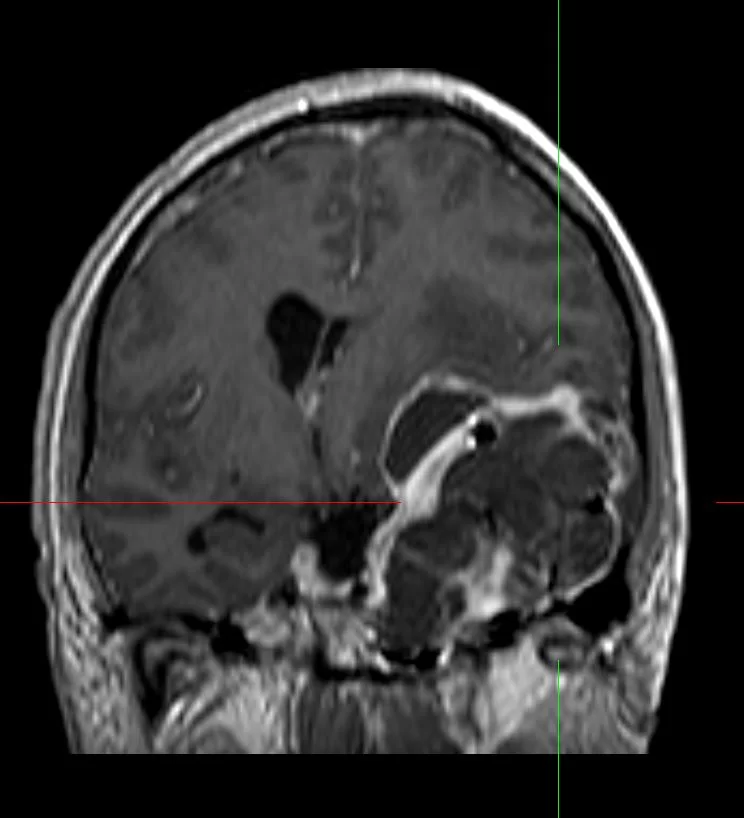

Η μαγνητική τομογραφία εγκεφάλου ανέδειξε εκτεταμένη χωροκατακτητική εξεργασία του μέσου κρανιακού βόθρου, πιθανότατα υποτροπή του δερμοειδούς όγκου για τον οποίο είχε χειρουργηθεί ο ασθενής το 1991.